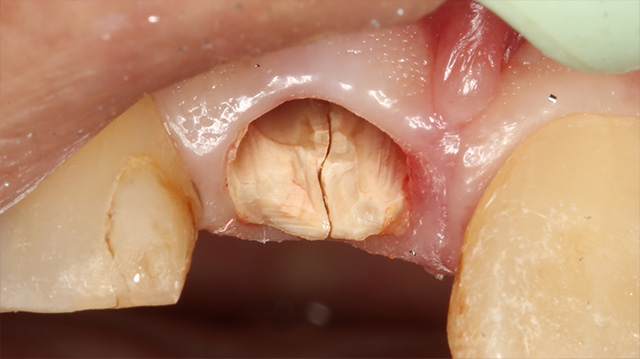

| 年代・性別 | 40代 男性 |

|---|---|

| 主訴 | 前歯の被せ物が取れた |

| 治療回数 | 3回 |

| 治療期間 | 約1ヶ月 |

| 費用 | 仮歯 5,500円 ジルコニアクラウン 176,000円 |